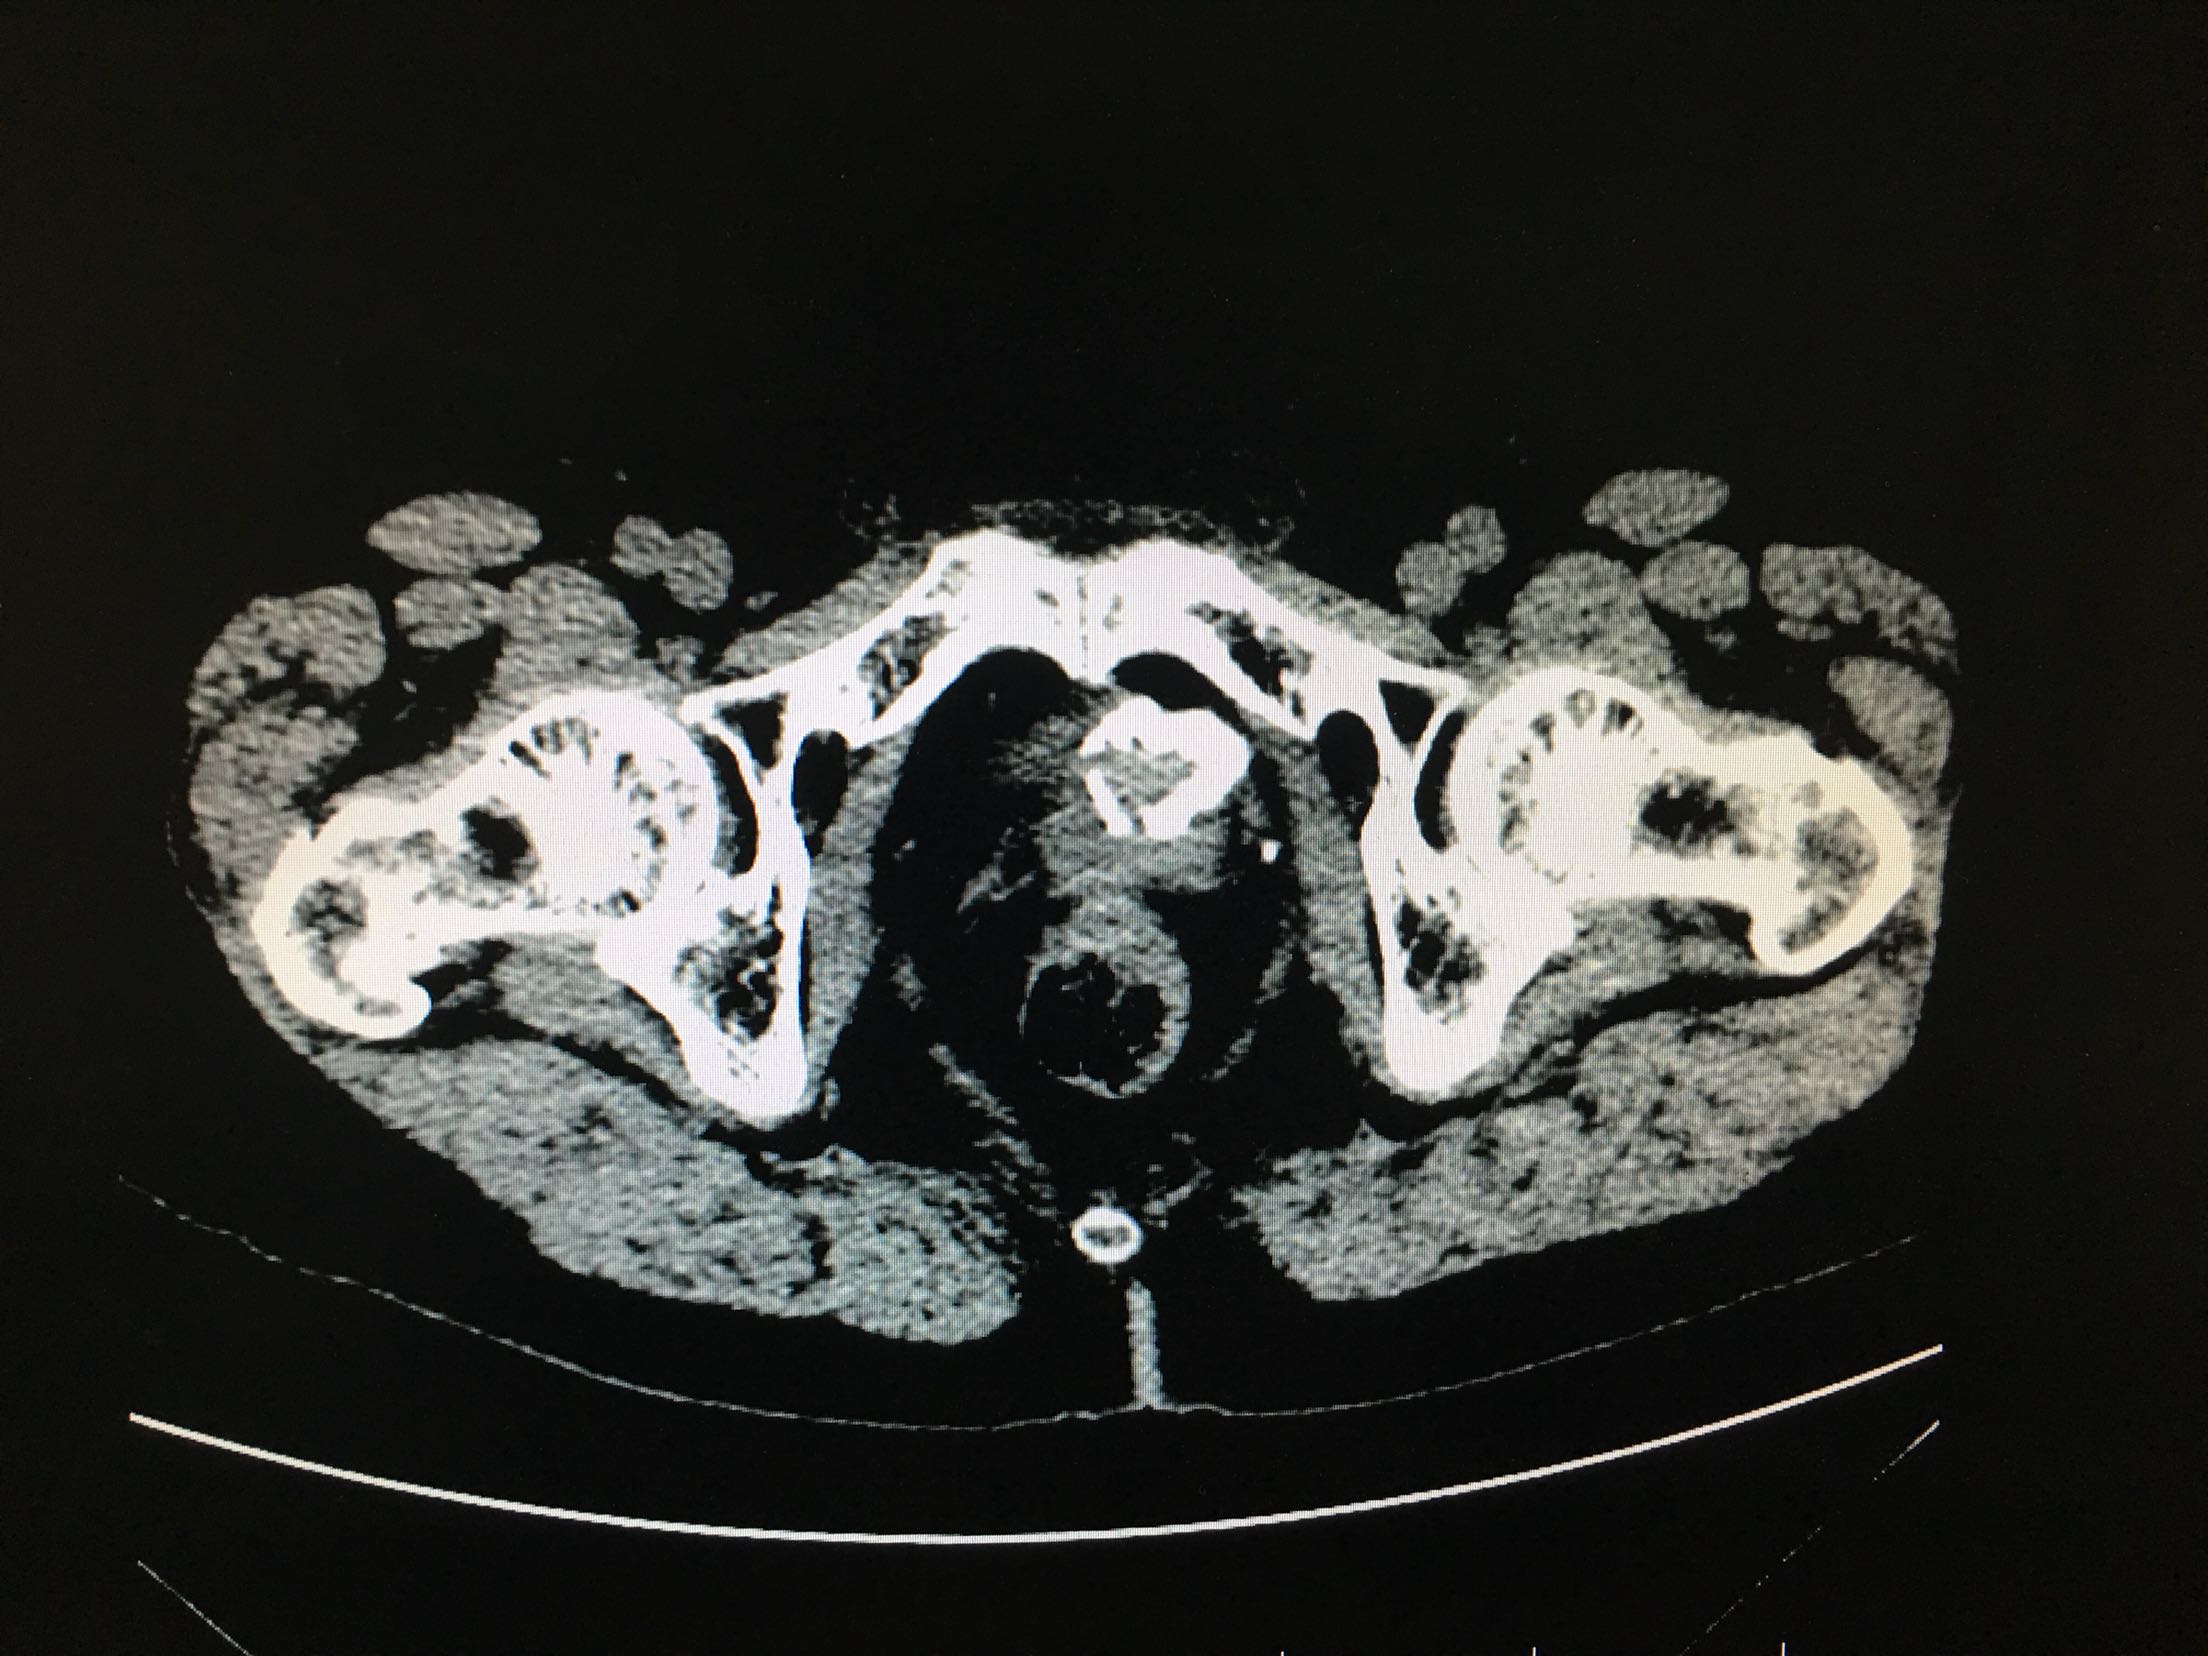

67岁男患者 2年前患者因为尿潴留检查发现前列腺癌,行经尿道前列腺癌电切改善排尿,术后给予内分泌治疗,5天前患者出现肉眼血尿,尿频、尿急、尿痛症状严重。患者为求进一步诊治来我院。患者发病以来精神状态差,体重减轻。

查体:双肾区无叩击痛,双输尿管走形区无压痛,耻骨上压痛,叩诊未见明确浊音。 辅助检查:ctu:膀胱占位性病变及直肠壁增厚,结合病史考虑前列腺癌伴膀胱及直肠受累。 psa:35ng/ml。